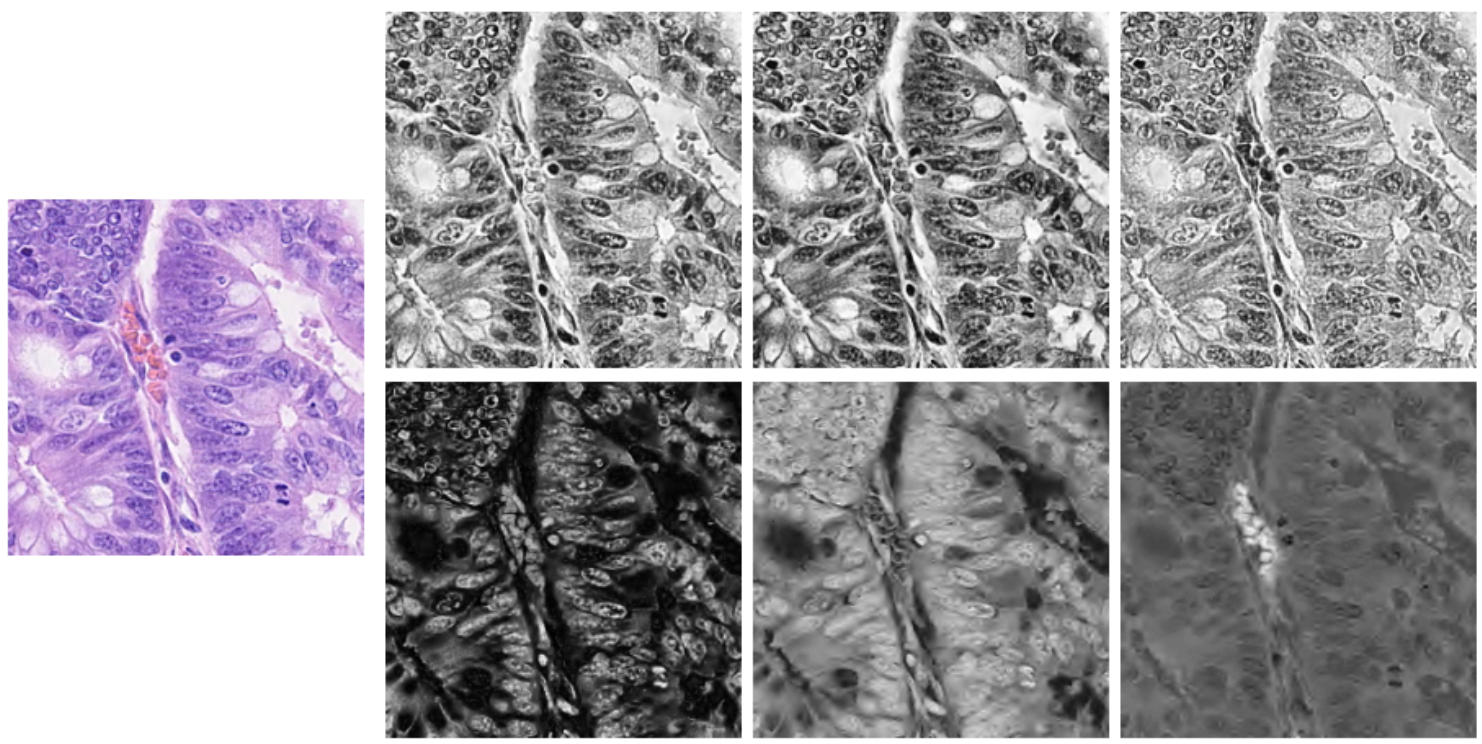

II-B Multi-channel color-stacking

Multi-channel color-stacking that combines the different channels from various color spaces is effective in detecting the fine features that help classify the different types of nuclei. We found that saturation (channel 2) in HSV color space, red-yellow and blue-yellow chrominances (channels 2 and 3) in YCrCb color space contained distinctive visual information not available in the RGB color space. Thus, these channels were merged to create a 6-channel input shown in Fig. 1.